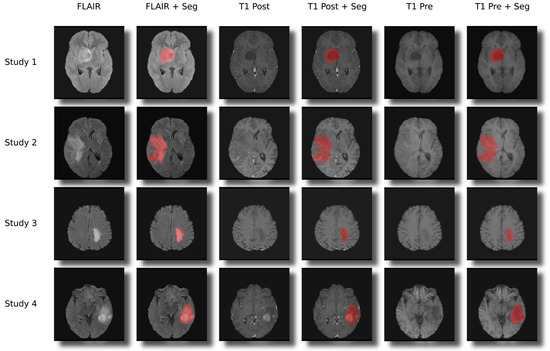

2.11. Validation of Segmentations